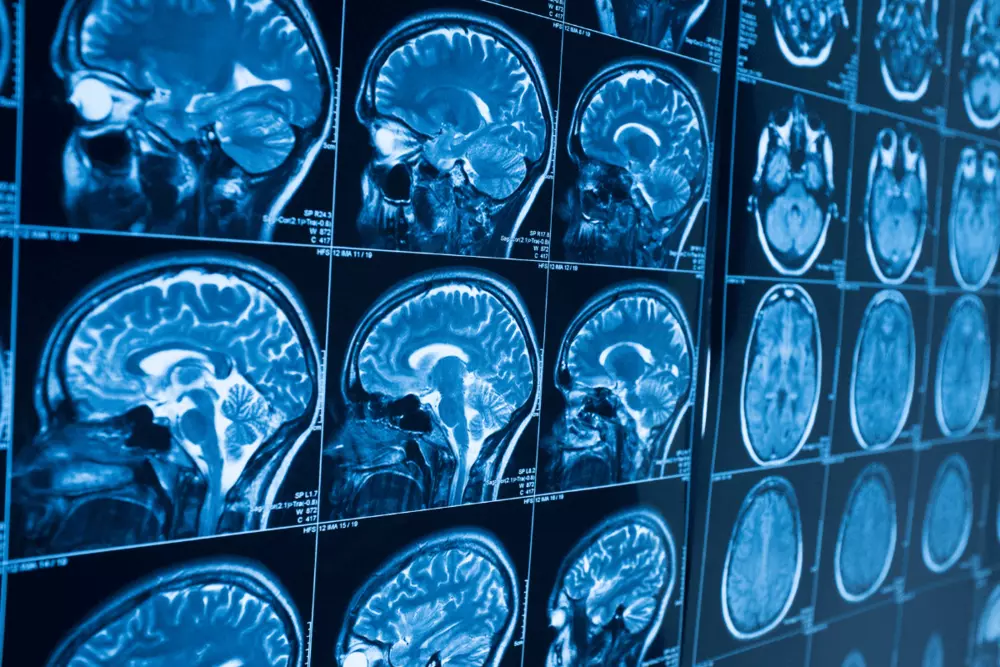

MRI腦部掃描影像

隨著磁振造影MRI 技術不斷進步,佳楠對低磁化率的無磁性連接器也持續進行相應改進以滿足醫療產業需求。不僅僅是醫療產業,我們還發現無磁性電鍍技術也適用於一些需要無磁特性的其他產業,如WIFI通訊、天線和測量設備。